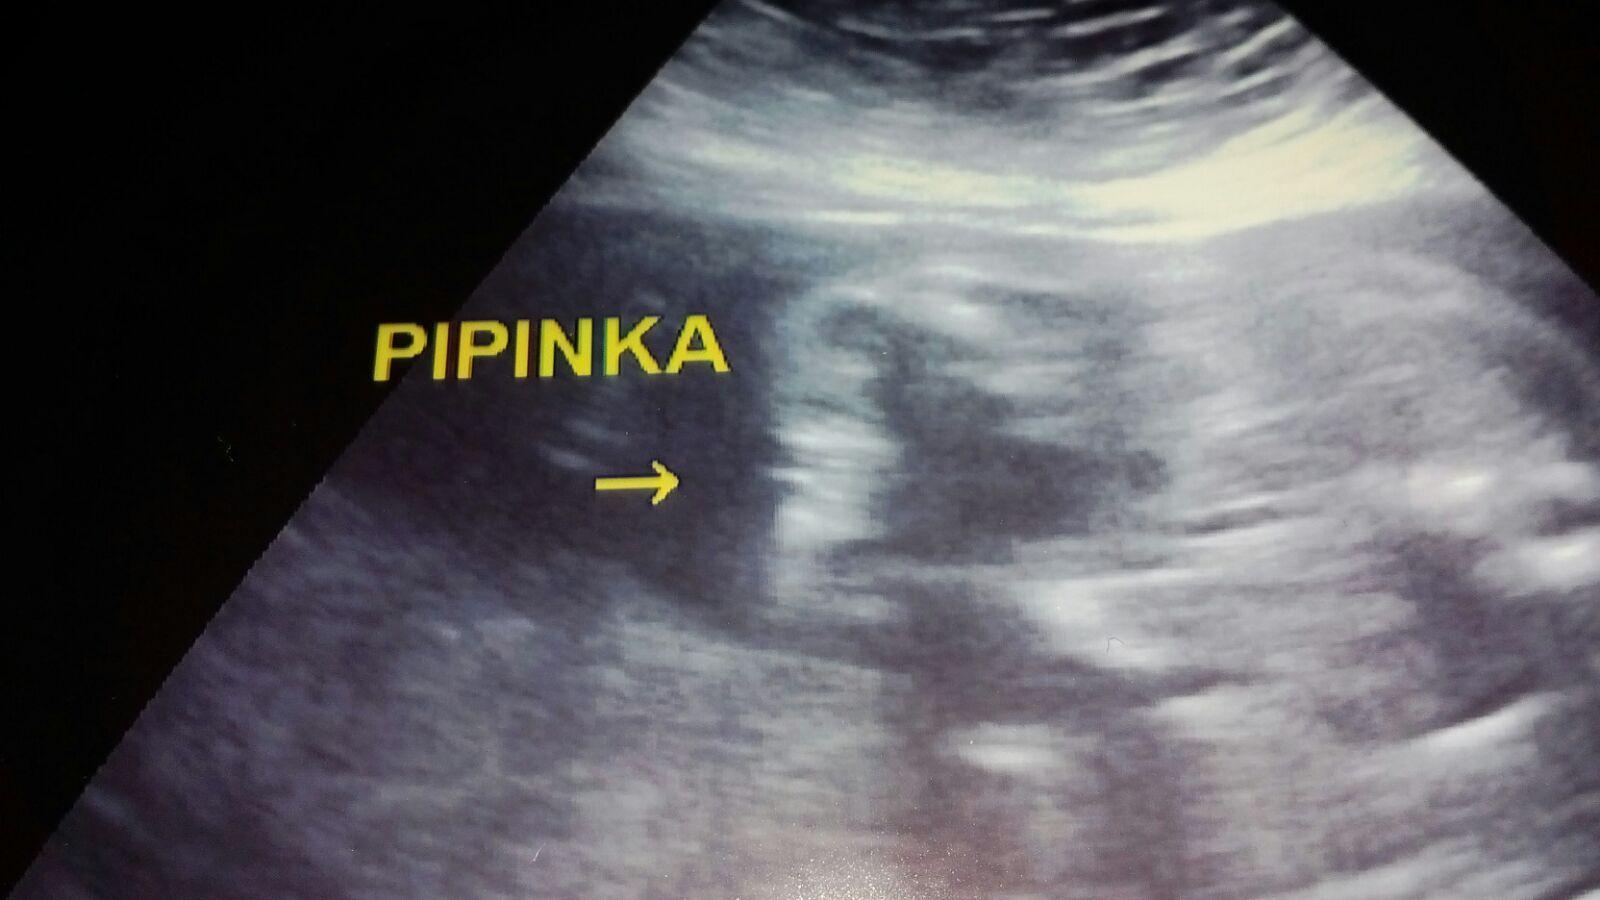

tak já se předevčírem dozvěděla, že čekáme chlapečka a to jsem ve 38. týdnu, za 14 mám jít rodit...doma 70% věcí růžových, protože mi doktorka tvrdila v 5. a 6. měsíci, že je to děvče. Už jsem rodině ani přátelům nic neříkala, ještě se s tím sama srovnávám :D no a vymýšlíme jméno pro chlapce.... i když mám obrázek z ultrazvuku a na něm jasný varlátka a pindík, čekám co z toho nakonec vyjde.... 🙂

@looolaaa to už je chlap..pindík zretelnej

@lujda661 podle utz to na kluka opravdu vypadá..

@lujda661 jasný kluk, máme stejnou fotku z utz v 16tt a je to kluk 😀